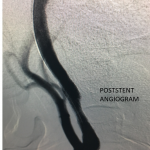

Figure 1.

This 77-year-old man with a history of stroke in 2013 presented to a small community hospital with aphasia upon awakening. Given the unclear timing of onset of his symptoms he was not deemed a candidate for intravenous thrombolytic. His NIHSS was 2 in the emergency room. He was admitted to the hospital where a CT (Figure 1) and CTA were performed showing a left frontal small infarct and severe extracranial carotid stenosis on the left. MRI could not be performed because of the patient’s pacemaker. Examination was significant for an awake gentleman with normal cranial nerve function and normal motor exam but significant expressive aphasia. Receptive aphasia was intact. He was placed on Aspirin.